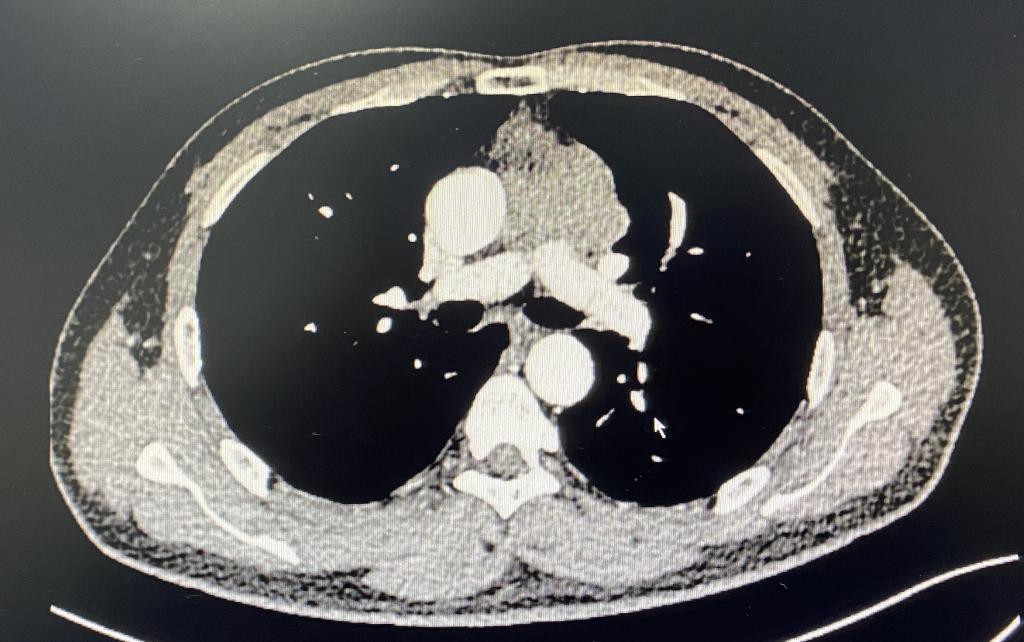

此位男性患者因声音嘶哑2月就诊,行胸部CT提示前纵膈可见不规则软组织密度,与主动脉弓、肺动脉主干和左肺上叶分界不清,大小约64mm x 18mm,于外院行穿刺活检示胸腺肿瘤,结合免疫组化考虑B型或AB型胸腺瘤。因手术难度大,肿瘤与周围重要组织和脏器关系密切,遂慕名转院来我院胸外科就诊。

根据最新研究显示:胸腺瘤是较常见的成人前纵隔肿瘤,好发年龄为30-50岁,男性发病率高于女性,且20%胸腺瘤患者伴重症肌无力,手术切除为首选的治疗方案,其病理组织学分型包括:A型、AB型、B型(B1、B2和B3)以及C型(即胸腺癌),均为恶性,其中C型约占10%。患者早期多无不适,当肿瘤长到一定体积时,对周围器官的压迫可出现相应症状。该病人因属于AB型或B型,虽低度恶性,但浸润性生长,因喉返神经受侵出现声音嘶哑才引起重视。患者入院后,李少民主任率领马震川、孔冉冉主治医师和李文登住院医师,制定详细手术方案。术中如预判的一样,肿瘤侵犯主动脉弓、肺动脉干、左肺动脉主干全段以及左肺上叶肺组织,肿瘤游离困难,遂打开心包,发现肿瘤已侵入心包,并与心包内左肺动脉干起始部粘连。手术完整游离切除肿瘤及部分心包,并行心包修补和肺部分切除,手术顺利完成。术后患者自感胸闷及压迫感明显减轻,恢复良好。

病例1:术前胸部增强CT